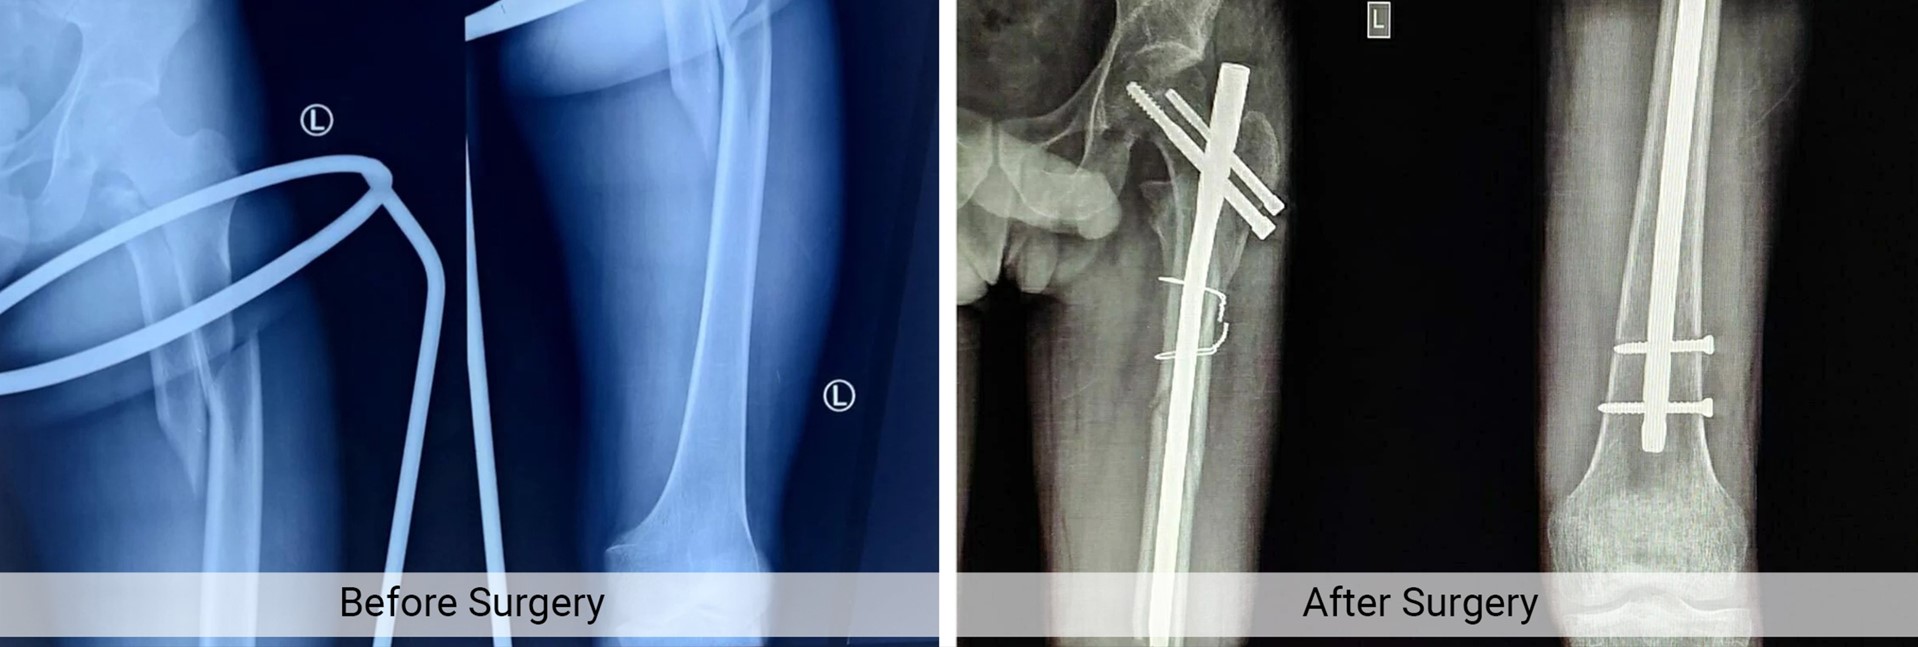

Trauma Fracture